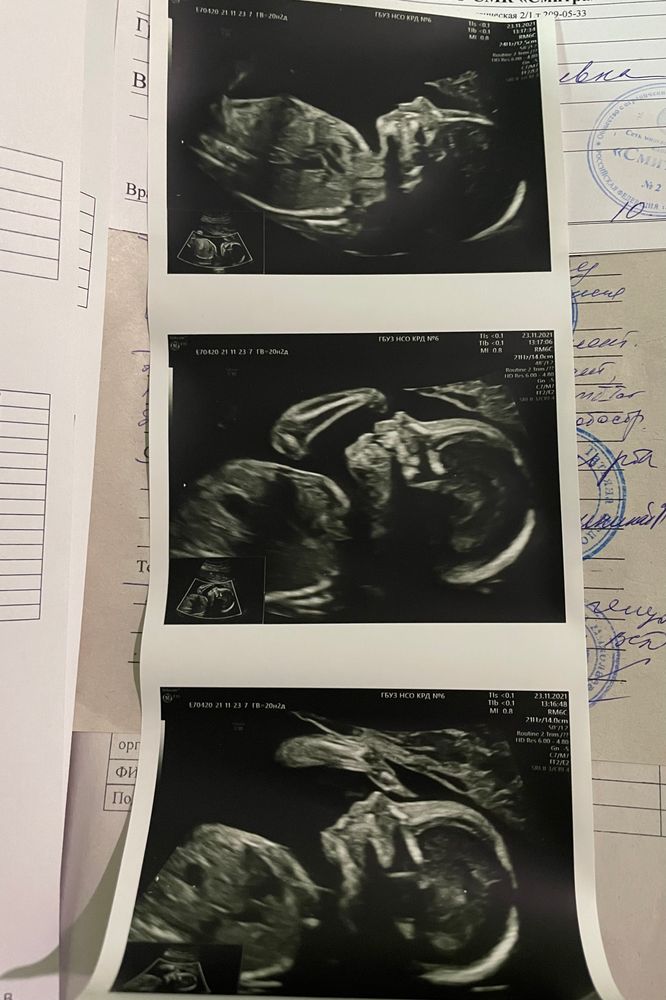

2 беременностьИ мы прошли второй скрининг. Девочкааааа!!👧🏻💖 Все показатели в норме. Показали ручки и ножки, вертимся конечно нормально)

Малышка с каждым днем все ощутимее шевелится, вчера уже даже видно было снаружи. На 24 неделе пойдем смотреть сердечко поподробнее